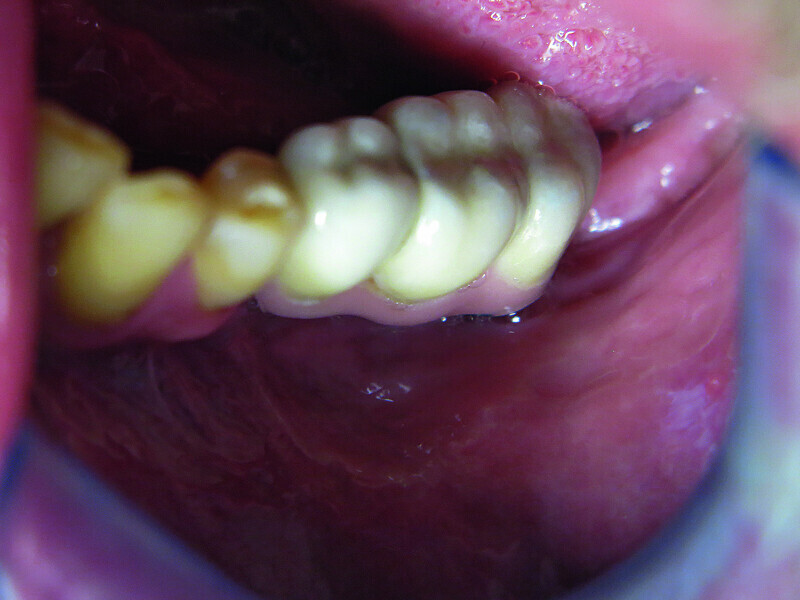

Fig. 12: Screwed on superstructure.